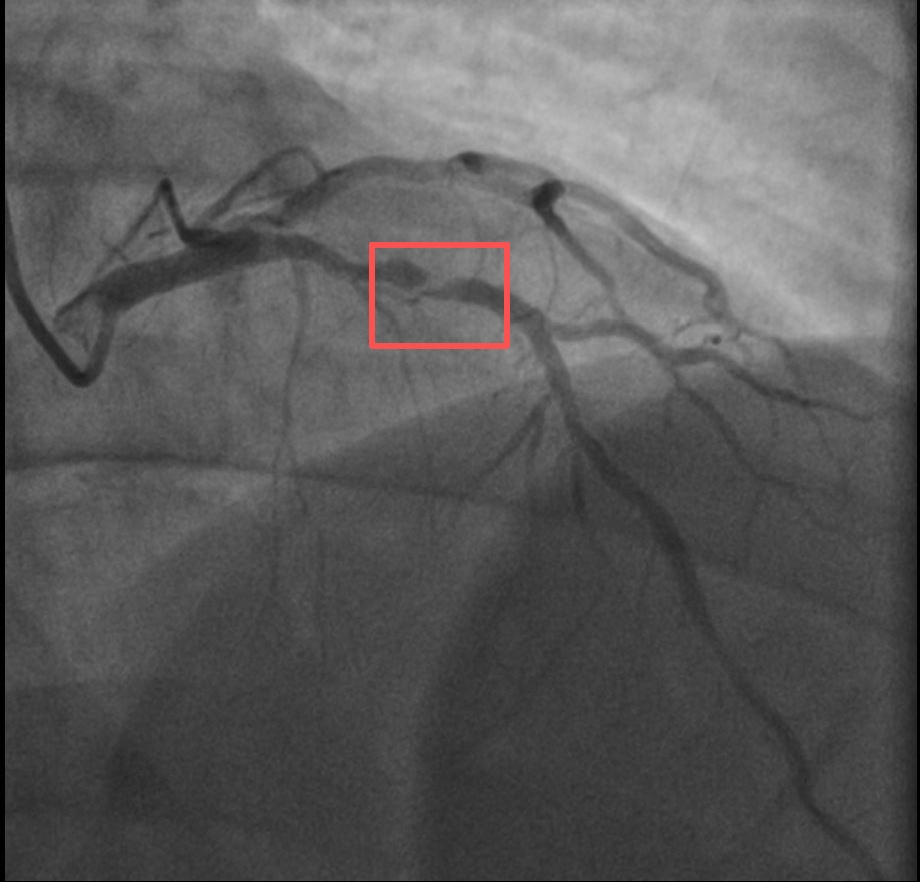

浙江医院心血管内科副主任汤益民主任医师分析,剧烈运动导致这位患者心脏的不稳定斑块破裂,进而造成前降支近段次全闭塞。所幸送医及时,孙先生的身体险情被成功化解。

介入治疗前后影像图